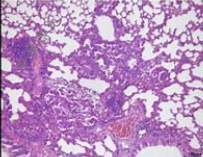

肺纖維化模型病理及纖維化檢測(cè):